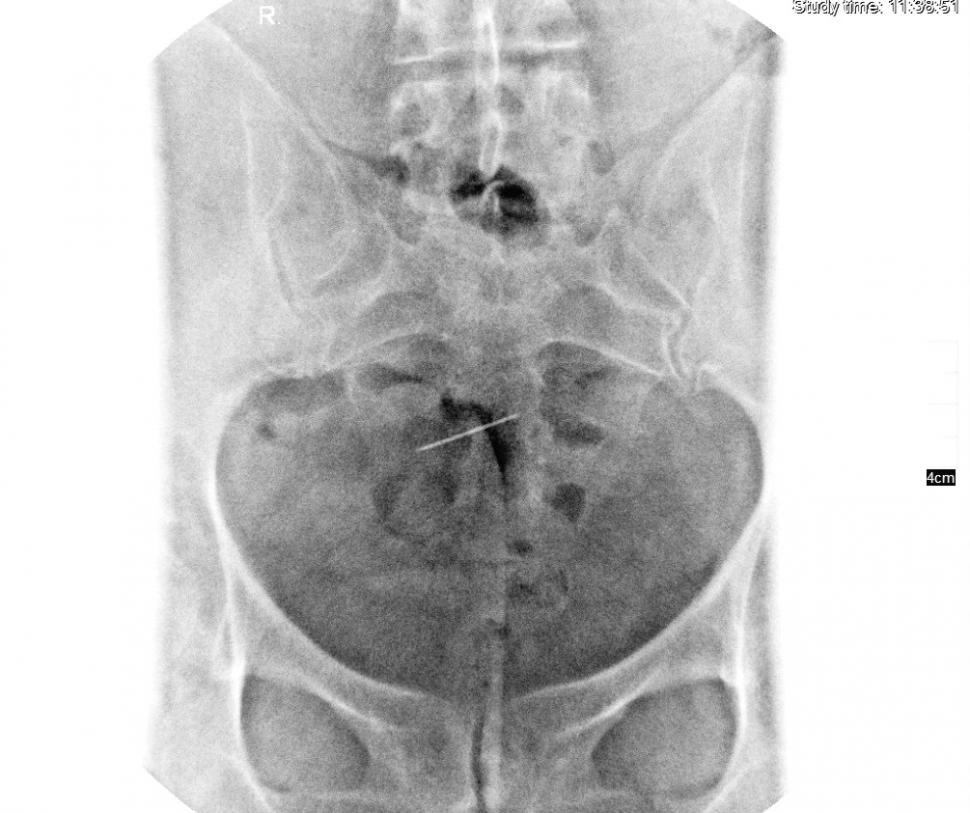

Femeia din Iași se simțea rău și s-a dus la medic. Specialistul a încremenit când a văzut ce apare pe radiografie. „Dumnezeule, e de 30 de ani acolo!” (FOTO)